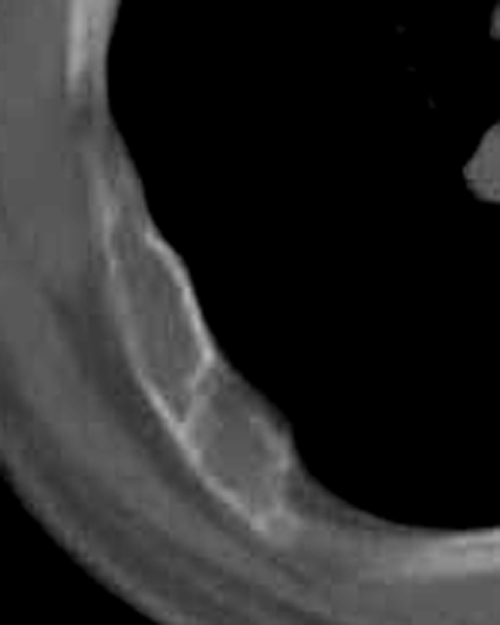

房**,38岁,间歇性胸疼2年

肋骨溶骨性破坏,皮质膨胀呈囊状,可见间隔,部分边缘硬化。考虑肋骨骨纤维结构不良。

膨胀性肋骨破坏,皮质连续。周围软组织无异常。良性占位。首先考虑骨纤。

膨胀性肋骨破坏,皮质连续,内无钙化。周围软组织无异常。良性占位。首先考虑  1骨纤  2内生性软骨瘤及骨囊肿待排

肋骨溶骨性破坏,皮质膨胀呈囊状,可见间隔,部分边缘硬化。考虑肋骨骨纤维结构不良。不除外浆细胞瘤。

肋骨溶骨性破坏,皮质膨胀呈囊状,可见间隔,部分边缘硬化。考虑良性病变,肋骨骨纤维异常增生症可能大

膨胀性肋骨破坏,皮质连续,硬化。周围软组织无异常。良性占位。首先考虑  1骨纤  2内生性软骨瘤